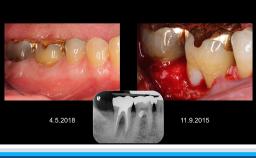

環境変化に対応する革新的アプローチ

インプラント治療において、急速な高齢化や低侵襲治療など患者のニーズの変化、審美へ要求、難症例の増加、デジタルの発展や歯科業界の全体の構造的な変化など激烈な変化が見られる。演者は革新的ななアプローチでどの様に対応するかについて解説する。